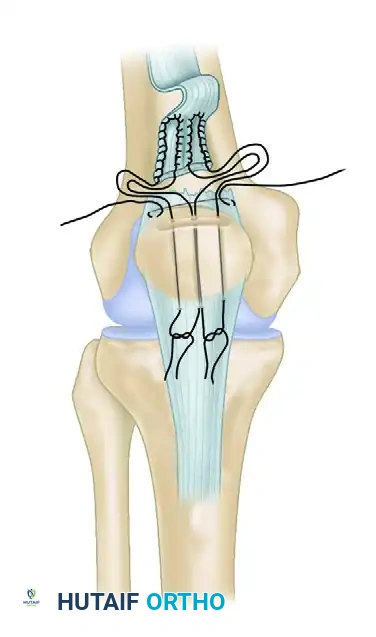

Suture Configuration and Passage (Transosseous Technique)

- Place two or three heavy, nonabsorbable sutures (e.g., #2 or #5 FiberWire or Ethibond) into the proximal tendon stump using a locked, running configuration (such as the Krackow, Bunnell, or Kessler technique). The Krackow technique is preferred for its superior biomechanical grip on longitudinally oriented tendon fibers.

- Ensure that the sutures grasp the rectus femoris, vastus lateralis, and vastus medialis components securely.

- Place separate horizontal mattress sutures in the deeper vastus intermedius stump if it has retracted proximally.

- Drill three parallel, longitudinal transosseous tunnels through the patella, starting from the prepared trough at the superior pole and exiting at the inferior pole. Use a 2.0-mm or 2.5-mm drill bit.

- Using a suture passer or a Beath pin, pass the free ends of the heavy sutures through the transosseous tunnels. The central sutures share the middle tunnel, while the medial and lateral sutures pass through their respective tunnels.

Tensioning, Tying, and Retinacular Repair

- Extend the knee fully.

- Apply distal traction to the quadriceps tendon to pull the tendon stump deeply into the prepared patellar trough.

- Pull the sutures anteriorly through the rectus and tie them securely at the inferior pole of the patella while the tendon is held in strict anatomical position.

- Assess the tension of the repair. The patella should track centrally, and there should be no gap at the repair site.

- Meticulously repair the medial and lateral retinacular tears using interrupted #1 or #0 absorbable sutures. This step is vital for restoring the dynamic tracking of the patella and reinforcing the primary repair.

- If the tissue quality is exceptionally poor, or if the repair is under undue tension, consider reinforcement. The repair can be protected by a circumferential cerclage wire, strong nonabsorbable sutures, or a Bunnell pull-out wire routed through the medial and lateral retinaculum.